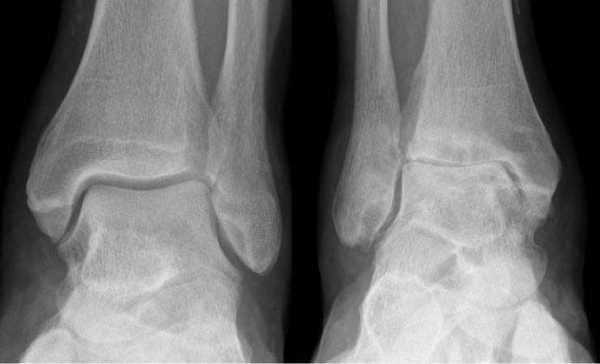

- Рентгенологическое обследование включает рентгенографию голеностопного сустава стоя в прямой, боковой и косой проекциях, а также рентгенографию стопы. Исследование важно выполнять с нагрузкой, только тогда оценка состояния конечности будет наиболее точной. Особого внимания заслуживают положение компонентов, признаки остеолиза и кистозной перестройки, переломы, костные дефекты и состояние подтаранного сустава и суставов стопы